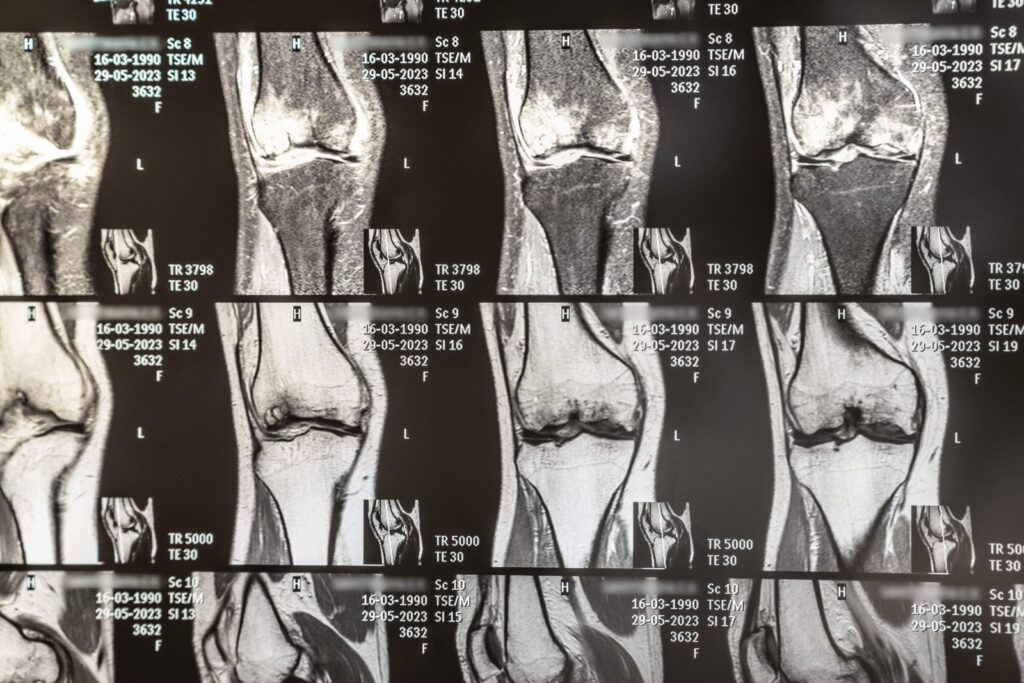

A ressonância magnética utiliza um campo magnético e ondas de rádio para criar imagens de alta definição das estruturas internas do corpo. Diferentemente do raio-X e da tomografia computadorizada, que são mais eficazes para visualizar ossos, esse exame se destaca na análise de tecidos moles, como:

Essa capacidade de capturar detalhes essenciais torna a ressonância magnética indispensável na identificação de lesões ortopédicas complexas.

Lesões ortopédicas podem ser difíceis de identificar com exames convencionais. A ressonância magnética é amplamente utilizada para diagnosticar: